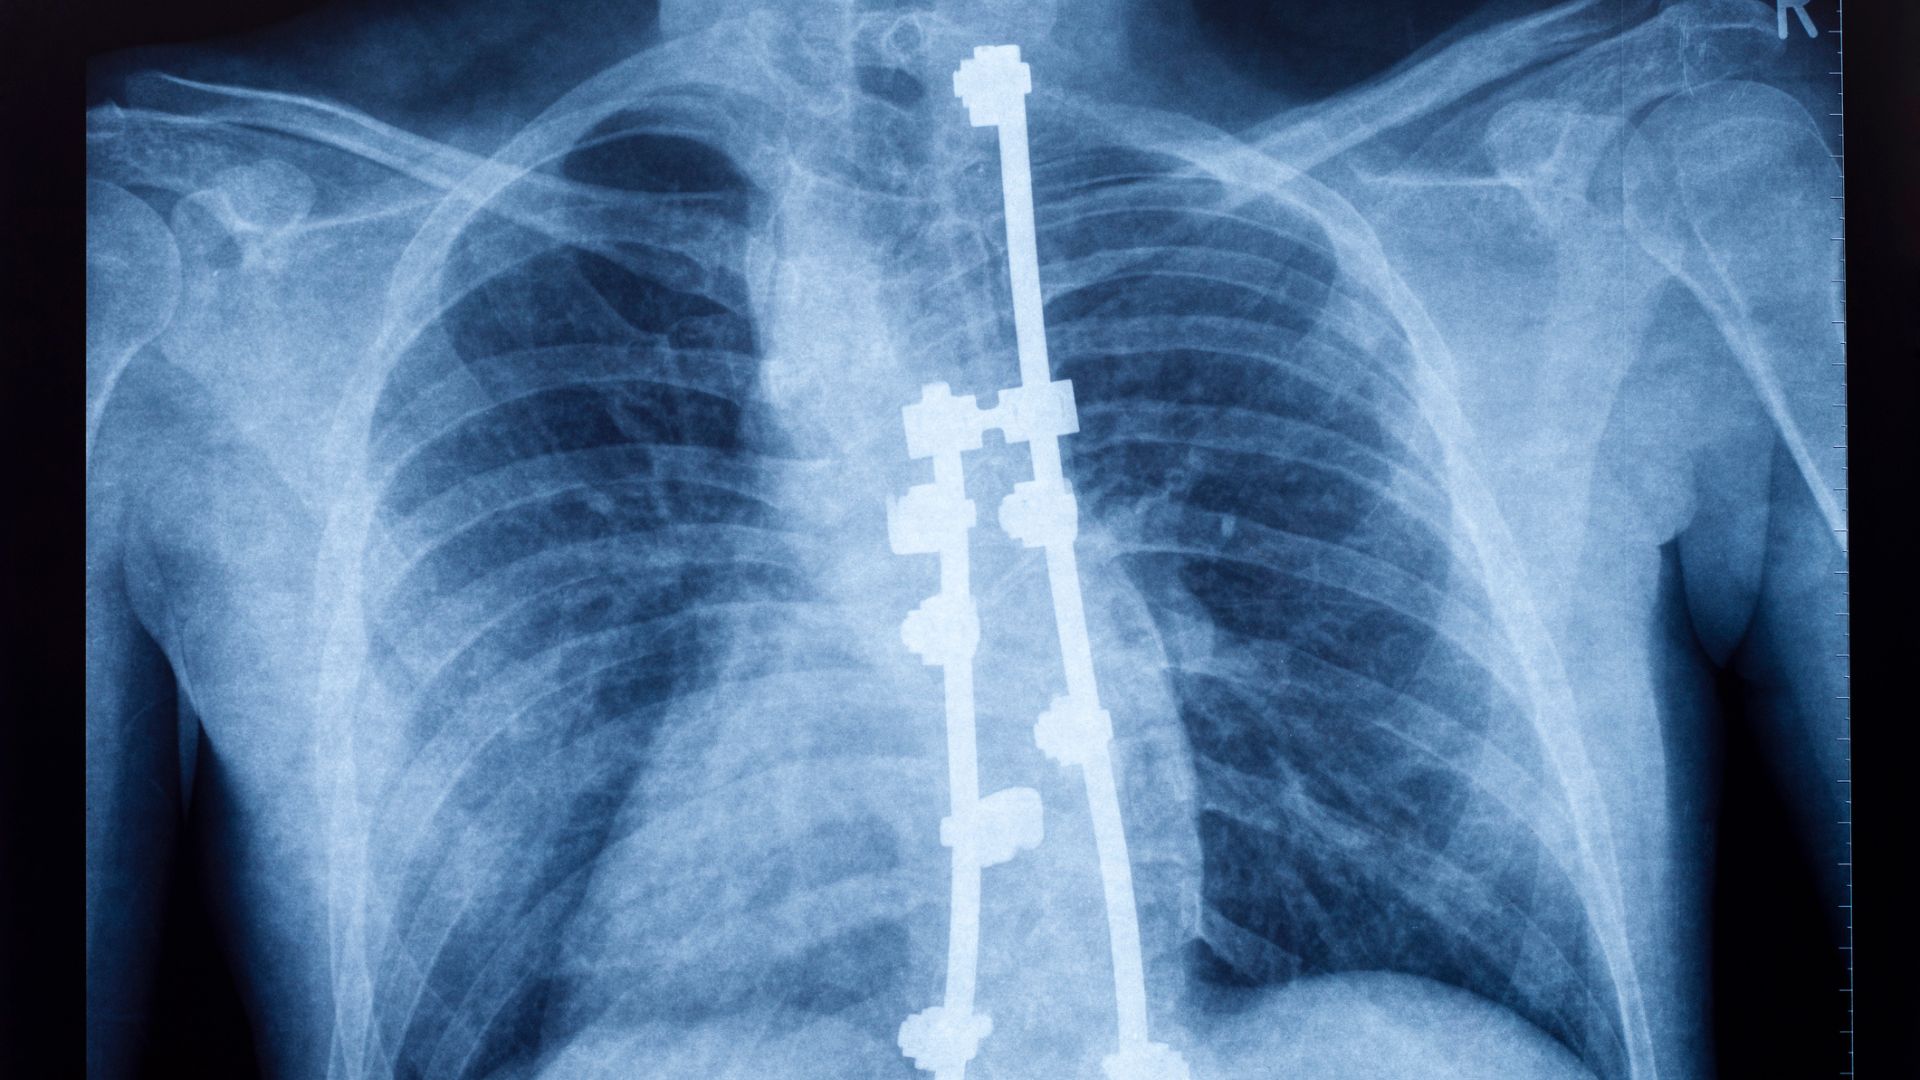

Researchers at the University of California, Riverside, have developed functional ultrasound imaging (fUSI) technology, which provides real-time high-resolution images of the human spinal cord during surgery. This innovation aims to enhance surgical procedures and improve medical treatments by allowing surgeons to view the spinal cord in detail while operating.